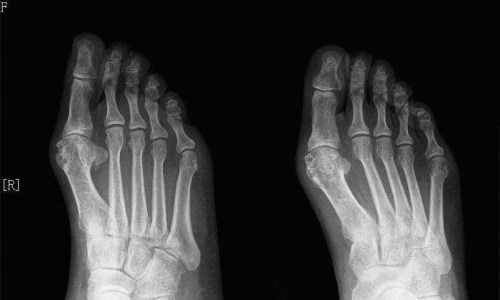

(图:患者既往X光显示右脚轻度变形且伴有痛风石)

查体:双手、踝关节轻度异常,右足第一趾关节痛风石溃破。